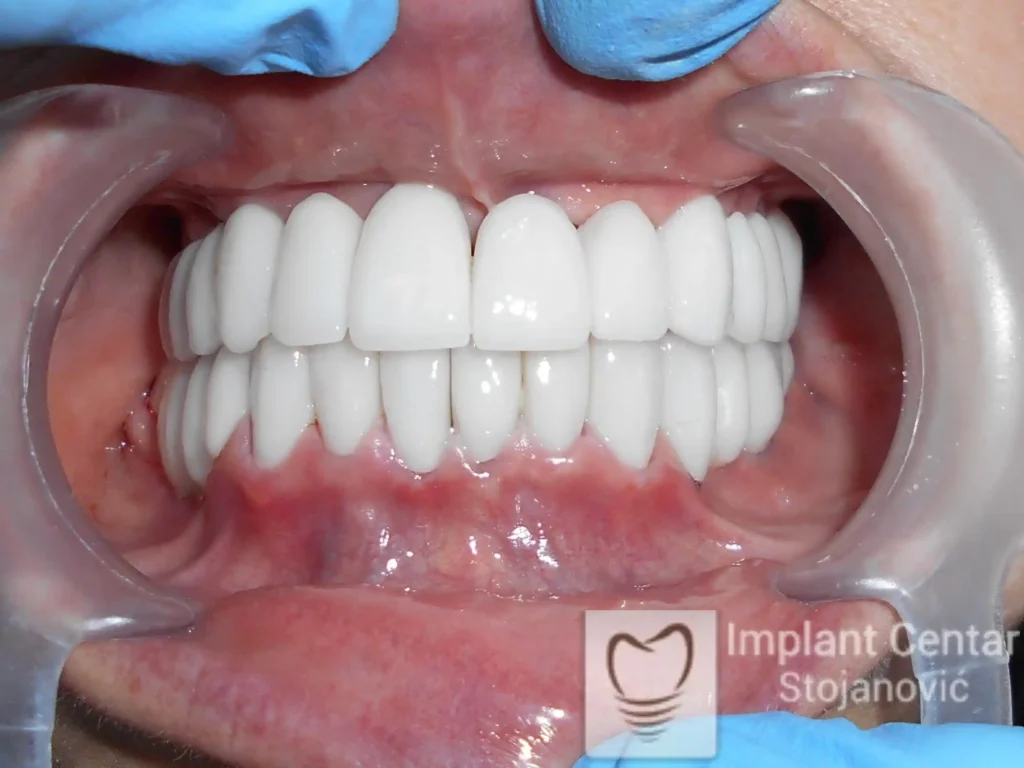

Nakon vađenja zuba, ugrađeni su implantati. Na slici 3 prikazan je ortopan snimak sa ugrđenim implantatima. Tokom perioda osteointegracije, pacijent je bio zbrinut fiksnim privremenim krunicama na implantatima, koje su izrađene samo dva dana nakon hirurške intervencije.

Na slikama 5. i 6. prikazan je izgled definitivnih cirkonijum-keramičkih mostova na implantatima.

Pacijent je izuzetno zadovoljan — kako estetikom novog osmeha, tako i funkcijom, jer ponovo može bez problema da jede i da se smeje.